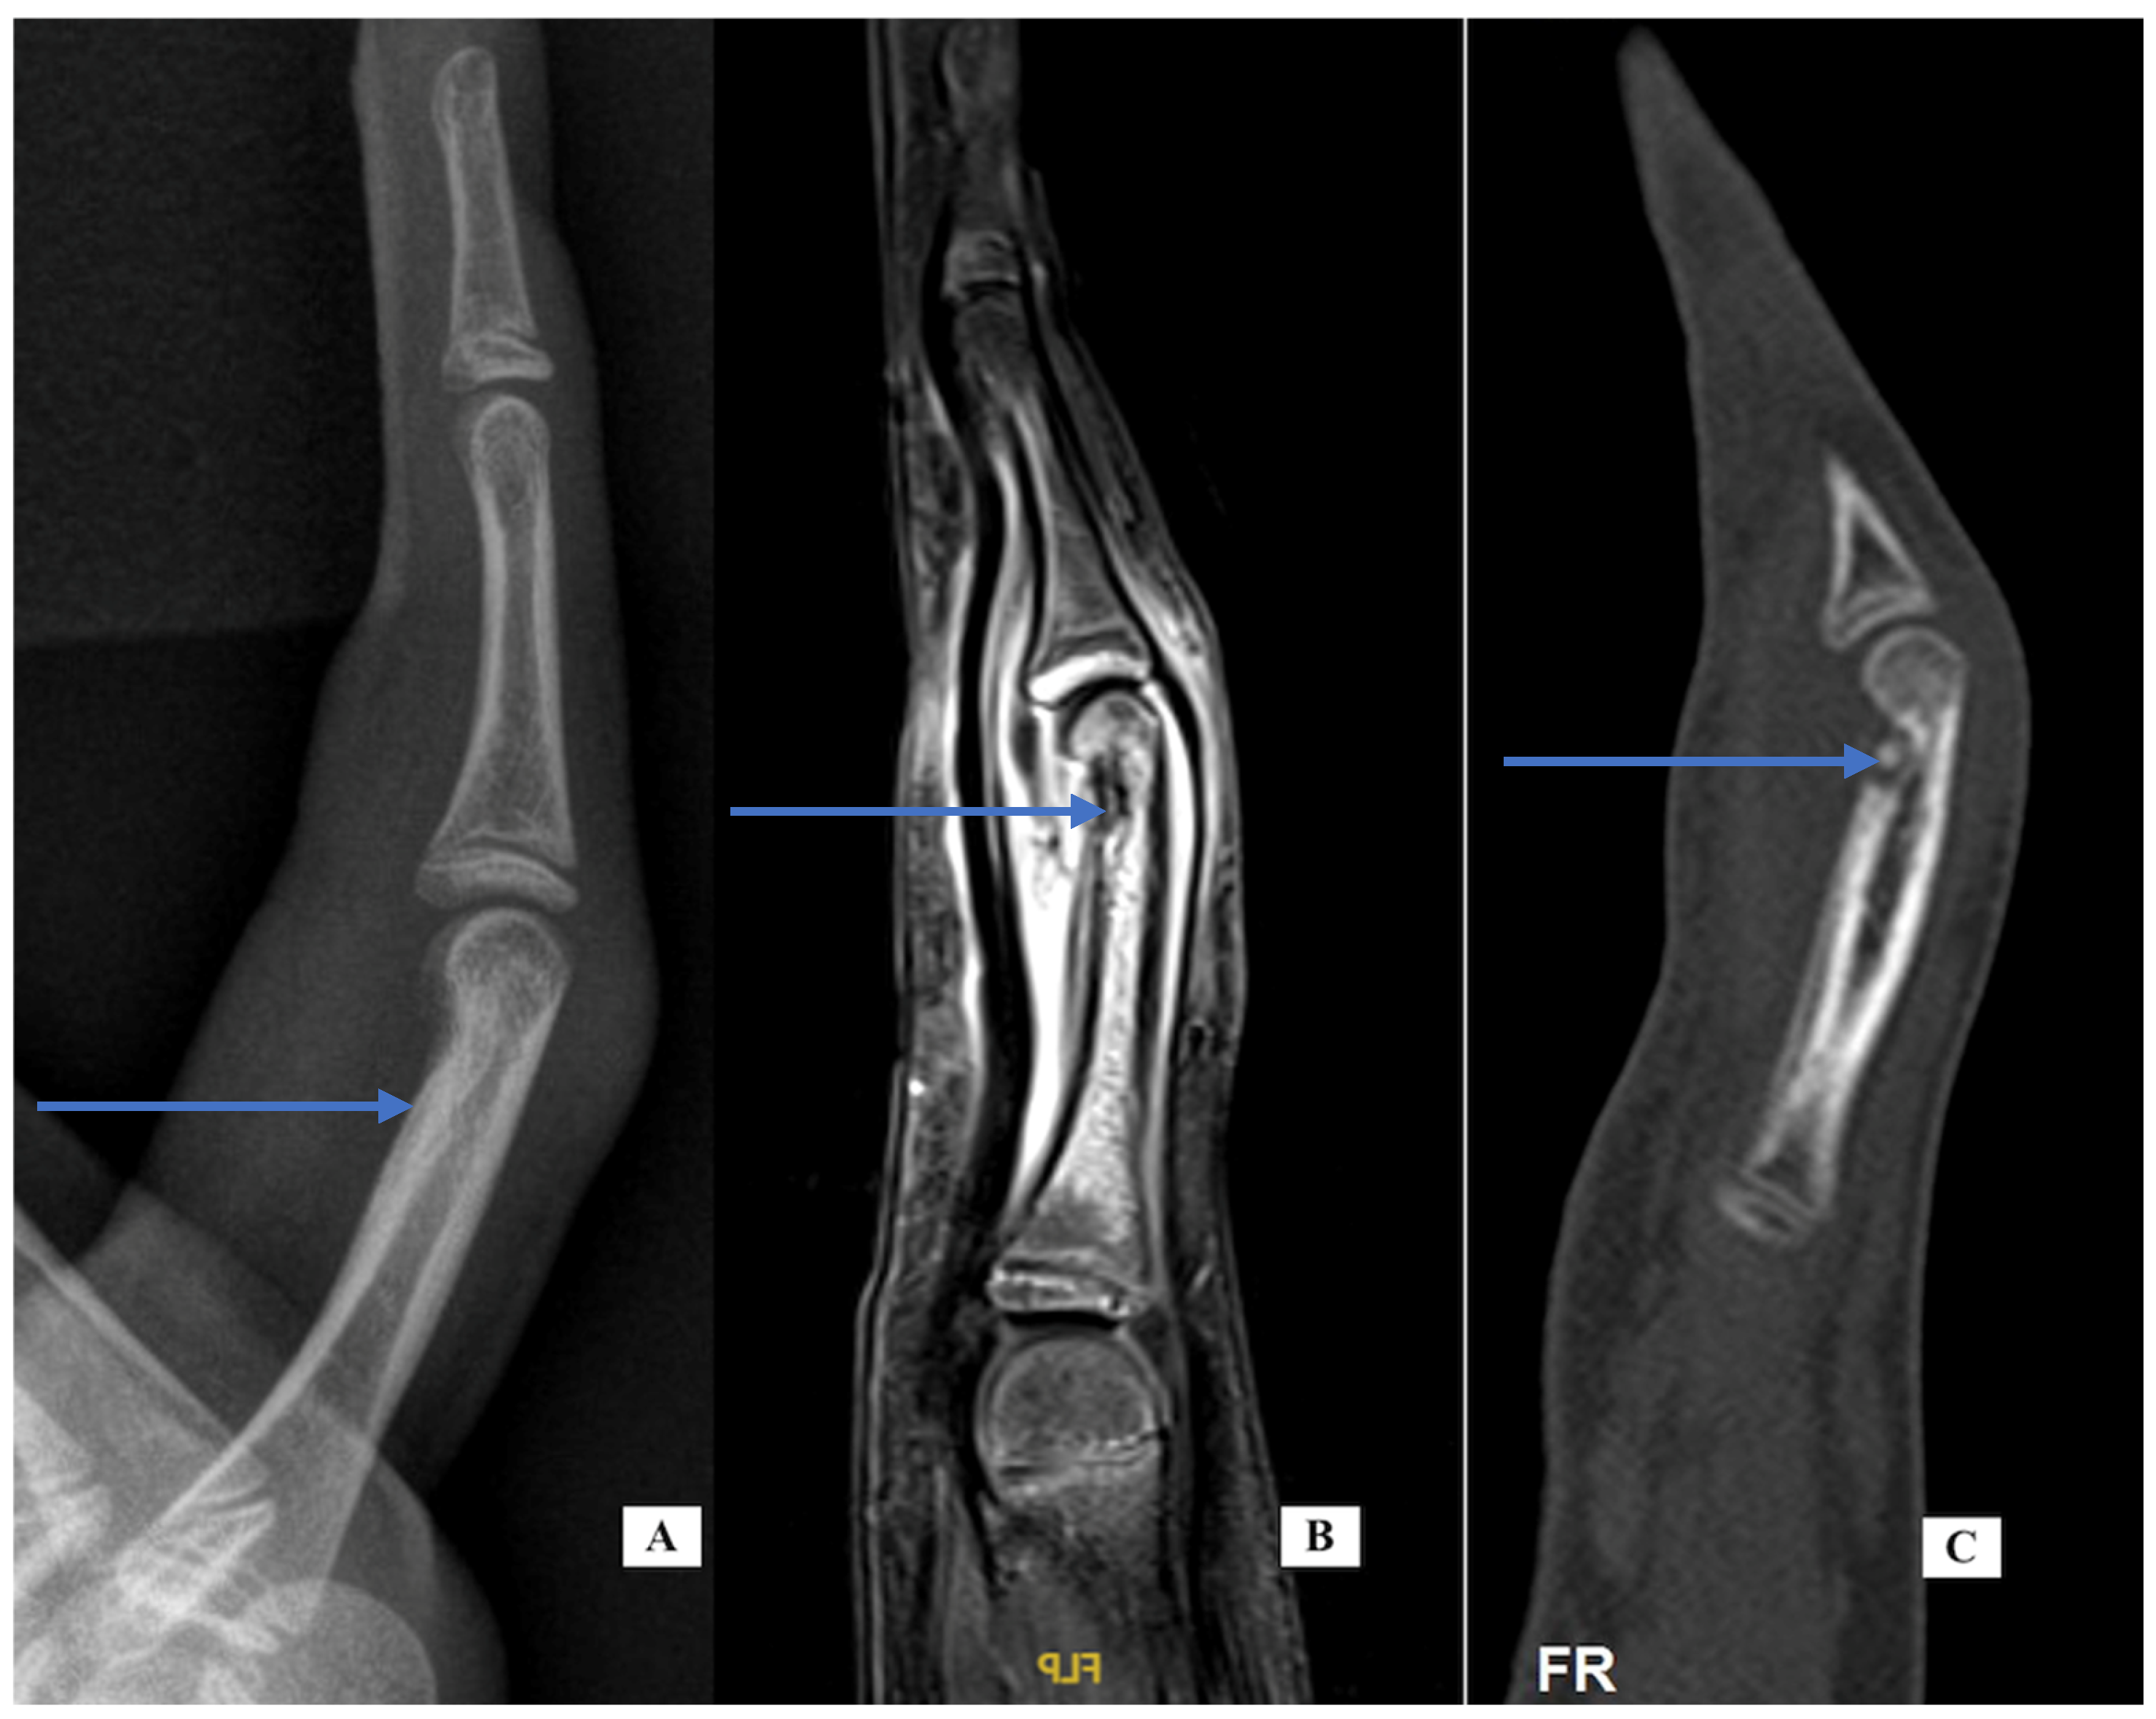

Case 1: A 22-year-old woman presented September 2018 with a 3-month history of right index finger swelling and stiffness localized to the PIP joint. There was no history of trauma and no other painful or inflamed joints. She had tried non-steroid anti-inflammatory drug (NSAID) medication, natural remedies, and occupational therapy, with no improvement. Her exam was notable for the swelling of the proximal phalanx and the PIP joint (Figure 1). She had mild PIP joint stiffness with flexion limited to 95 degrees (versus 105 degrees left F2). All labs for routine inflammatory screening (Table 1), X-rays and ultrasound were normal. She was sent for an MRI scan in October 2018 (Figure 1 center, post-contrast T1 fat suppressed) that demonstrated flexor tenosynovitis, joint synovitis and bone marrow edema. The report noted that “infection could not be ruled out”. She was taken to surgery (November 2018) with exploration under wide-awake local anesthesia no tourniquet (WALANT) for incisional biopsy of the thickened tenosynovium, both superficial and deep to the FDP tendon. The material was noted to be fibrotic and opaque in appearance. The material was sent for pathology, as well as cultures that included atypical mycobacterium. A specimen was sent for polymerase chain reaction (PCR—16S rDNA) testing. All the tests and cultures from surgery were negative, with pathology showing “nonspecific mild chronic inflammation” with a suggestion that “further clinical correlation is needed”. She was sent for a formal rheumatology evaluation and based on her presentation, psoriatic arthritis was suspected, and she was started on Sulfasalazine, which she took for 3 months without any improvement, so she elected to discontinue the medication. She adds that she had had no skin lesions in the past or on examination that would be consistent with psoriasis. Repeat labs for an underlying inflammatory disorder were carried out and again found to be normal. Repeat X-rays were carried out of her finger in January 2019, 6 months after the initial X-rays that showed soft tissue swelling, mild joint narrowing, and thick periosteal reaction involving the distal proximal and middle phalanges. Because there was still no improvement and no definitive diagnosis, a CT scan was performed. Her CT images from June 2021 (Figure 1, right) showed erosive changes at the PIP and DIP joints consistent with psoriatic arthritis. The CT findings were helpful in establishing a diagnosis and guiding future therapeutic options including starting biologics.

Figure 1. Case 1—clinical photograph of the enlarged PIP joint (A); MRI of the finger, sagittal view (B) demonstrating bone marrow edema at the base of P2; CT scan of the finger (C) demonstrating central erosions at the DIP joint (white arrow) and dorsal erosion at the PIP joint (blue arrow).